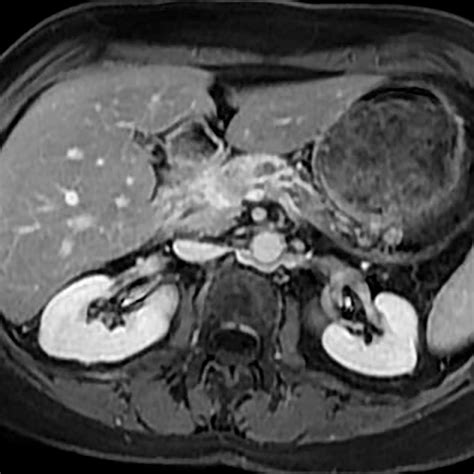

Pancreatic adenocarcinoma is a particularly aggressive form of pancreatic cancer that originates in the exocrine cells of the pancreas. Early detection and accurate diagnosis are crucial for effective treatment. One of the most important diagnostic tools for pancreatic adenocarcinoma is the Pancreatic Adenocarcinoma CT Scan. This imaging technique provides detailed images of the pancreas and surrounding tissues, helping healthcare professionals to identify tumors, assess their size and location, and plan appropriate treatment strategies.

A Pancreatic Adenocarcinoma CT Scan is a non-invasive imaging procedure that uses X-rays to create detailed cross-sectional images of the body. These scans are particularly useful for diagnosing pancreatic adenocarcinoma because they can:

• Detect tumors in the pancreas.

• Determine the size and location of the tumor.

• Assess the extent of the cancer's spread to nearby organs and lymph nodes.

After the Pancreatic Adenocarcinoma CT Scan, a radiologist will review the images to look for any signs of pancreatic adenocarcinoma. The results will be sent to the referring physician, who will discuss them with the patient. The scan results can provide valuable information, including:

• The presence and location of any tumors.

• The size and shape of the tumor.

• Whether the tumor has spread to nearby organs or lymph nodes.

• Magnetic Resonance Imaging (MRI): MRI uses magnetic fields and radio waves to create detailed images of the body. It can provide more information about soft tissues and is often used in conjunction with CT scans.